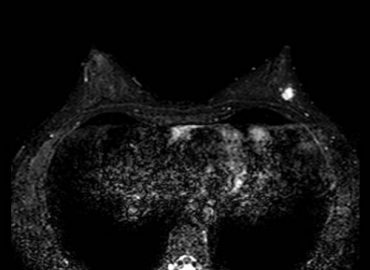

Antecedentes: – Sexo femenino – 50 años – MC: nódulo autopalpable en CSE MI. – Examen mamario: dos nódulos en […]